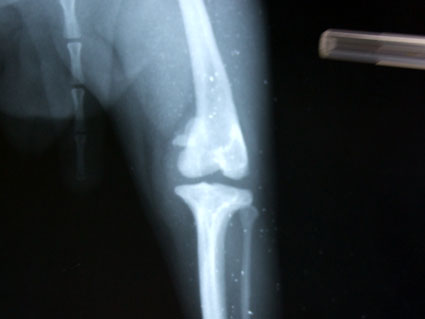

手術前,醫生先替茶茶拍X光片.

要開刀的這邊關節,韌帶已萎縮,狀況真的不太好.

所以醫生說要切斷原本的韌帶,裝上新的人工韌帶.